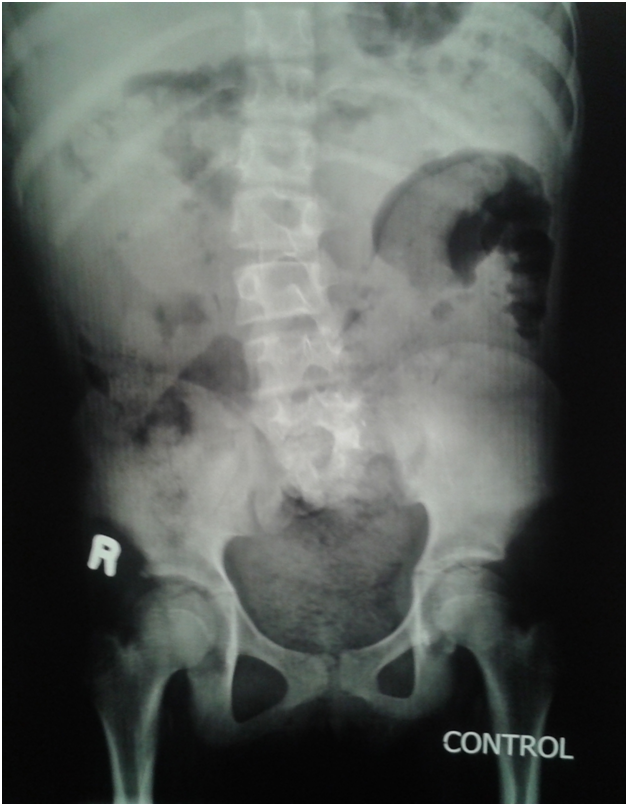

An eleven year old girl was presented to with chronic constipation, persistent dribbling of urine and recurrent urinary tract infections since early childhood. She received treatment by local physicians but remained without proper response. On examination, child was a febrile and her bladder was palpable. Her buttocks were flattened (Figure 1) and external genitalia were wet and excoriated. Anal tone was found decreased on digital rectal examination and the rectum was loaded with hard stool. No definite neurological deficit was found. She was catheterised and stool evacuated with per rectal enema. Her blood analysis showed low haemoglobin (8.1gm %), leucocytosis and raised serum creatinine level (2.2mg %). Urine analysis showed plenty of pus cells and growth of E. coli. Ultrasonography suggested bilateral hydro uretoronephrosis (rt>>lt) with loss of cortico medullary differentiation on right kidney and thickened irregular bladder with significant post void residual urine. Tc-99m DTPA renogram shows poorly functioning right kidney and satisfactorily functioning left kidney. Complete sacral agenesis, 5th lumbar vertebral atrophy and scoliosis with convexity towards right side seen in the control film (Figure 2) while neurogenic bladder with bilateral grade V vesico- ureteric reflux revealed on Voiding phase cystourethrogram (Figure 3). Child was further evaluated with urodynamic study, which suggested an overactive bladder in filling phase (Figure 4). Repeat blood analysis shows (Figure 4) normalisation of serum creatinine (1.2mg %). Her catheter has been removed and she has been placed on self clean intermittent catheterisation along with anti cholinergic (oxy butinine 5mg/daily) and laxative.

Figure 2 Complete Sacral agenesis, 5th lumbar vertebral atrophy.

Figure 3 Complete Sacral agenesis, 5th lumbar vertebral atrophy

Present report is a neglected case of sacral agenesis who presented late at 11years of age. Constipation and urinary incontinence was main complaint and on evaluation she found to have type III sacral agenesis, overactive bladder with bilateral reflux disease leading to kidney injury. High index of suspicion and some clinical clues like flattened buttock and short gluteal folds,9 are helpful for early diagnosis to avoid social stigma of urinary incontinence and to prevent kidney injury.